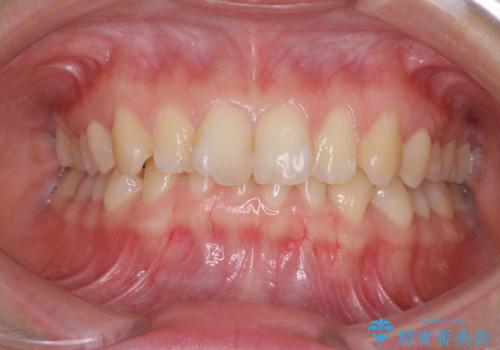

前歯のガタガタを目立たずきれいにしたい インビザラインによる見えない矯正

前歯の歯並びが気になる マウスピース矯正 30代女性